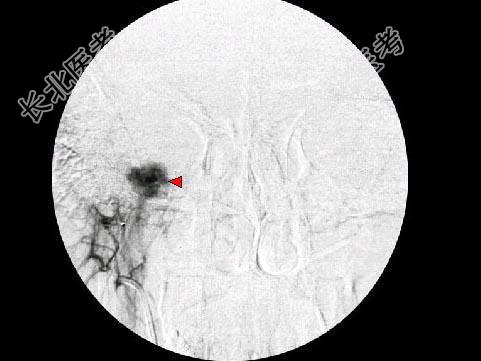

- 单项选择题男,45岁, 左侧搏动性耳鸣半年,耳镜检查透过鼓膜后下部见半膨隆紫红色肿物, CT如图,最可能的诊断是 ( )

E、颈静脉球瘤